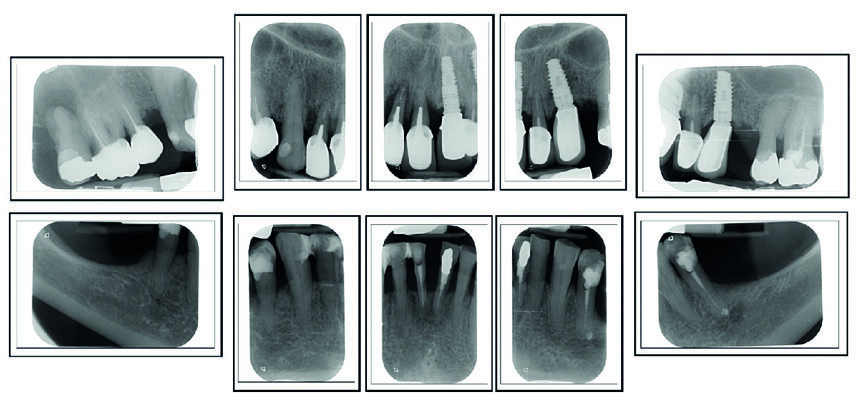

Me M. Ler, âgée de 71 ans lors de la chirurgie, ne présente pas d’antécédents médicaux particuliers, à l’exception d’un cholestérol stabilisé avec des statines (Tahor 10). Elle est traitée depuis 2007 pour une parodontite sévère qui est aussi globalement stabilisée cliniquement, radiologiquement et bactériologiquement. Nous avions déjà réalisé un traitement implantaire en 21 (2008) et 23 (2013) (Fig. 2). La patiente souhaite maintenant mettre des implants en 11 et 12 car les mobilités modérées de ces dents commencent à la gêner dans sa vie quotidienne.

Le volume osseux dans ce secteur est bon et ne présente pas d’infection (Fig. 3). Le choix s’oriente vers une implantation par chirurgie guidée avec mise en charge immédiate.

Fig. 2 : Bilan radiologique « long-cône ». Notez la sévérité des pertes d’attache, mais qui sont bien stabilisées depuis 12 ans.

Fig. 3 : Radiographie long cône du secteur à implanter. Notez l’absence d’infection et la bonne intégration de l’implant en 21, posé en 2008.

La patiente est revue à huit jours. Les suites opératoires se sont bien passées et la prise d’antalgique très limitée. Les sutures sont retirées. Puis la patiente est revue en contrôle à deux mois (Fig. 8), trois mois (Fig. 9) et quatre mois. Les radiographies de contrôles montrent un gain osseux au niveau de l’implant en 12 et une parfaite intégration des deux implants. Les cicatrisations clinique et osseuse sont très bonnes et il est décidé de passer à la prothèse définitive. Les couronnes et piliers provisoires sont retirés et les tissus mous vérifiés (Fig. 10).